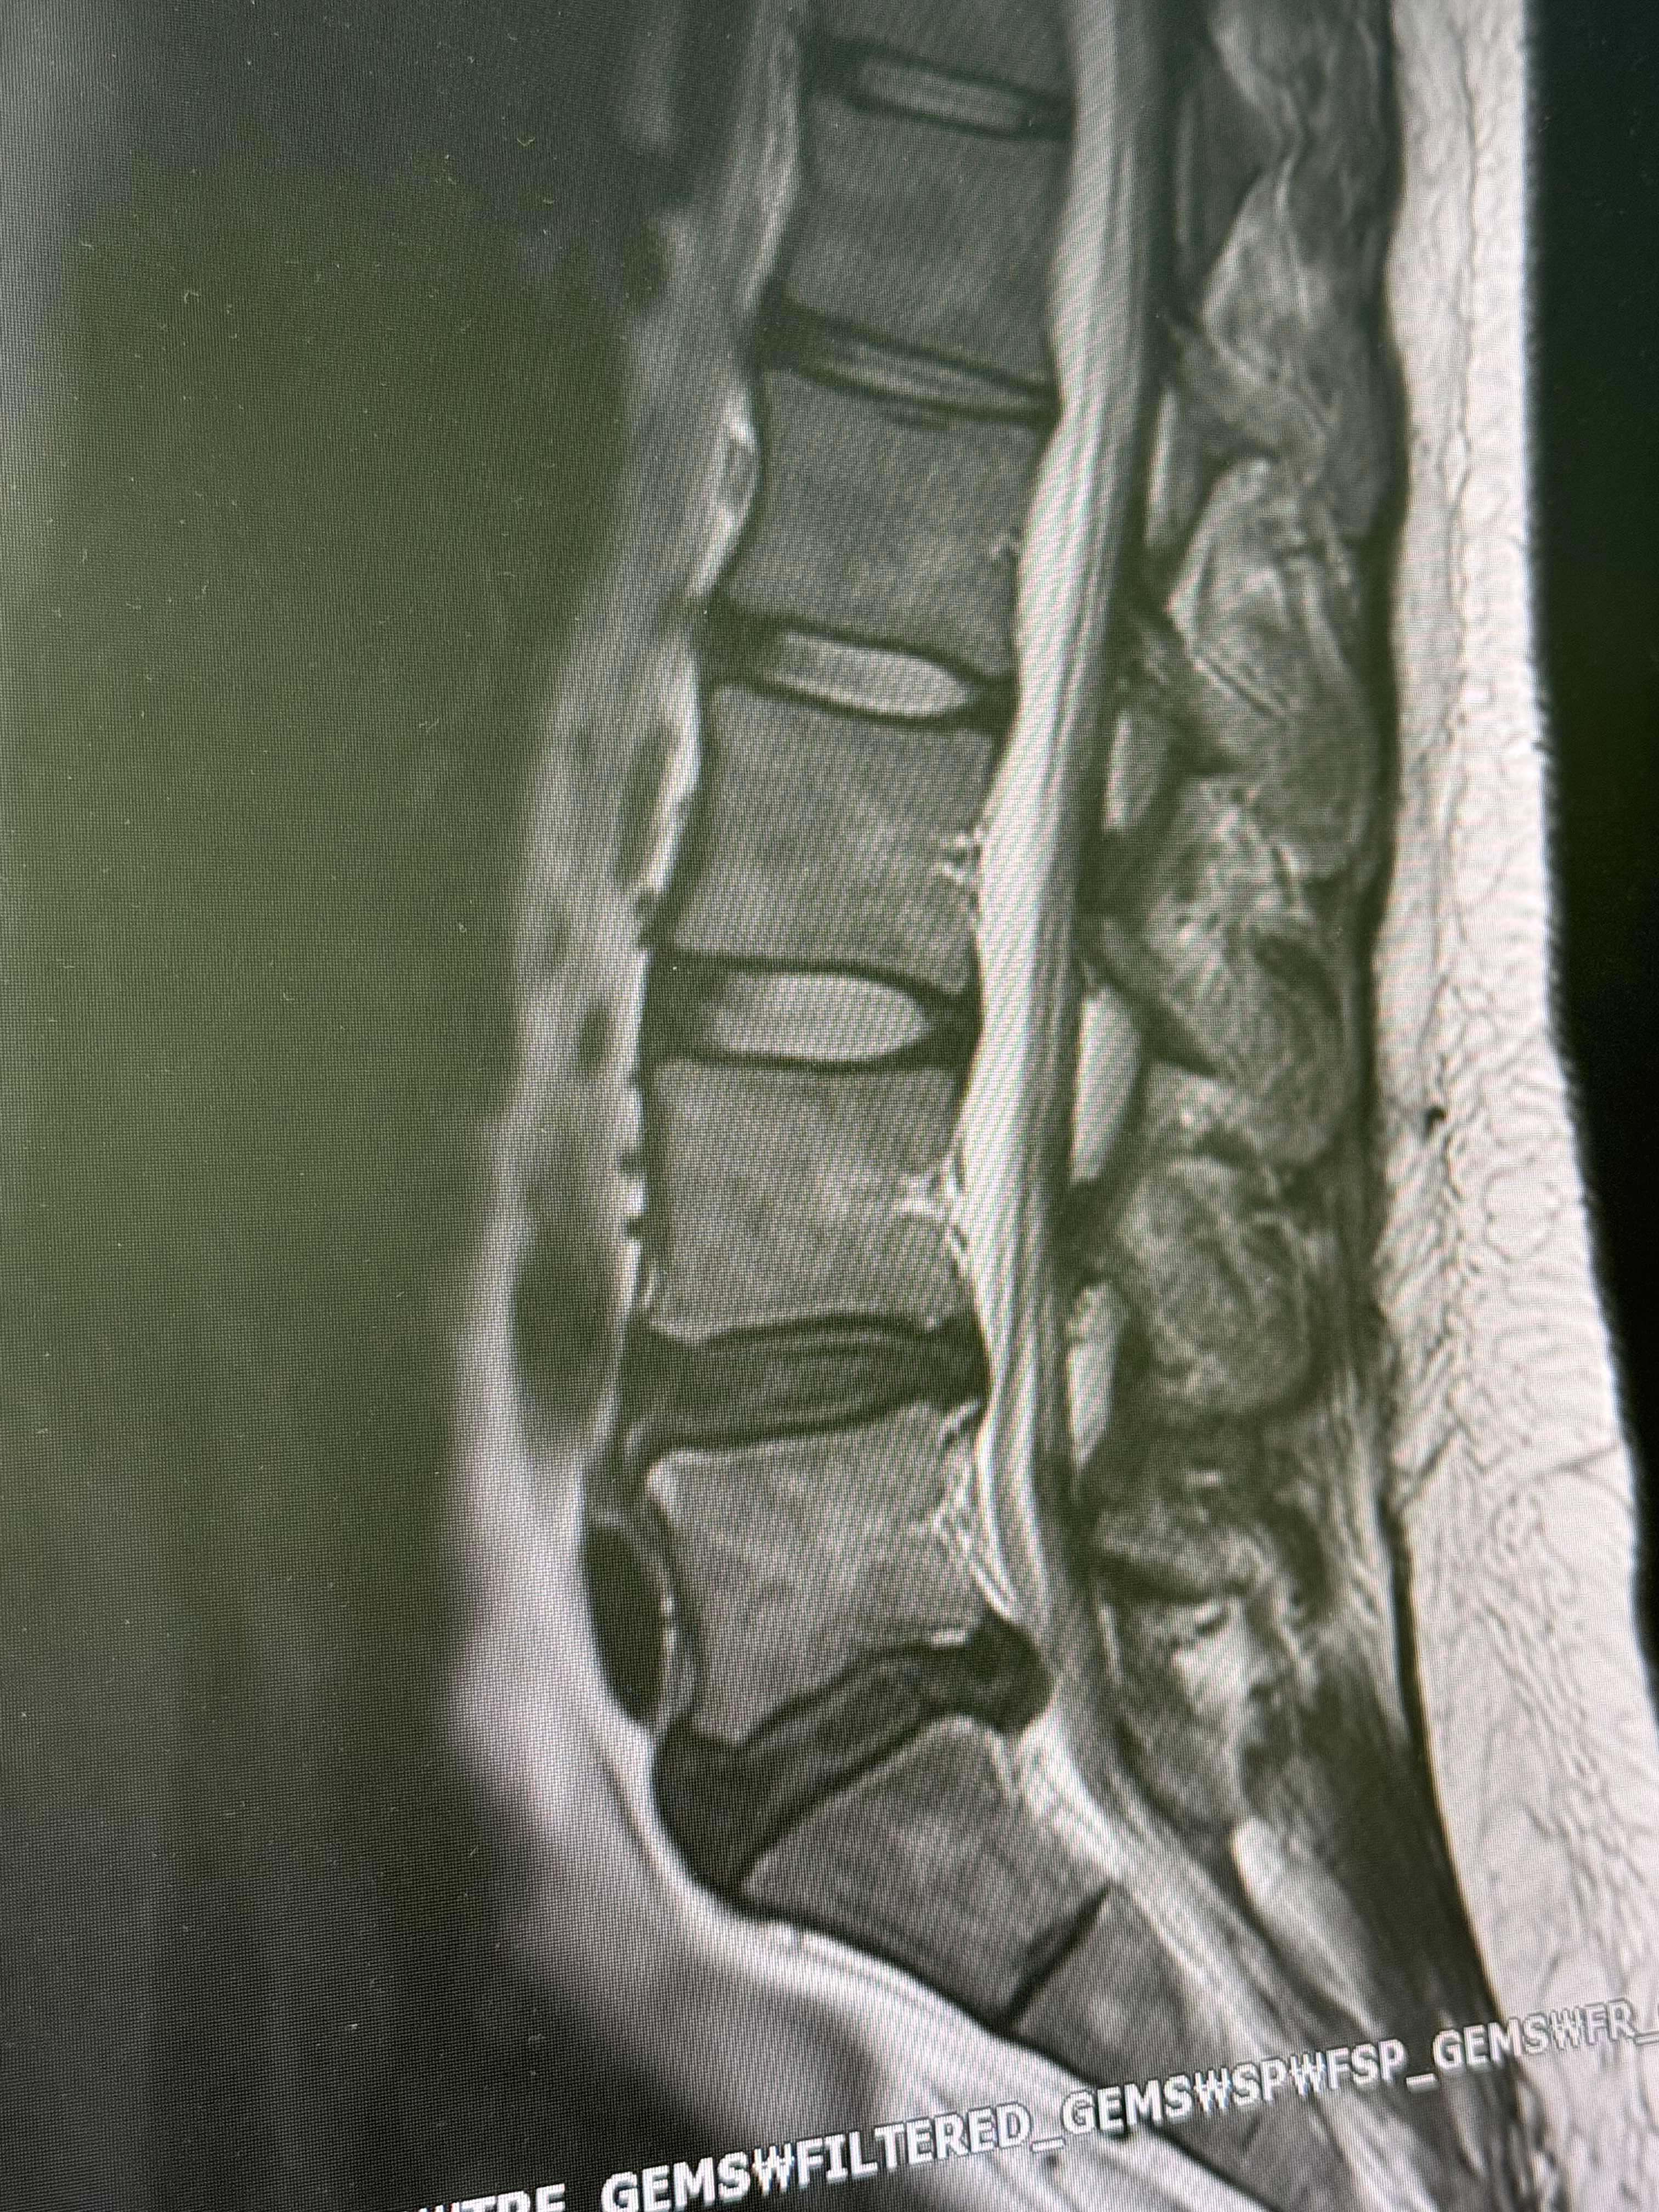

제 척추상태는.. 이랬습니다!!!!!!